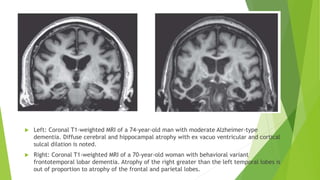

 Left: Coronal T1-weighted MRI of a 74-year-old man with moderate Alzheimer-type

dementia. Diffuse cerebral and hippocampal atrophy with ex vacuo ventricular and cortical

sulcal dilation is noted.

 Right: Coronal T1-weighted MRI of a 70-year-old woman with behavioral variant

frontotemporal lobar dementia. Atrophy of the right greater than the left temporal lobes is

out of proportion to atrophy of the frontal and parietal lobes.